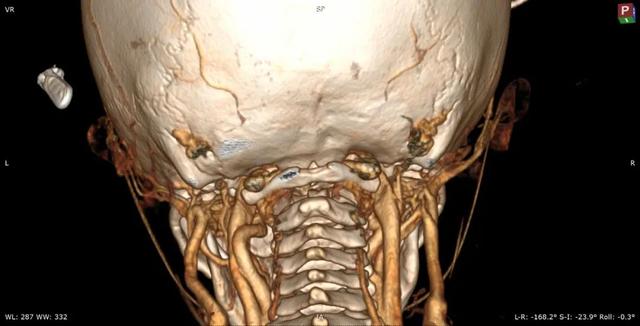

al-align:top;”> 孩子,望你早日康复! 这是一个关于 2岁宝贝的故事 为何这个幼儿平地摔倒,外表毫无受伤痕迹,却出现全身瘫痪,甚至呼吸功能衰竭? …… 为何凌晨时分,重医一院急诊科传来了救护车急促的汽笛声? …… 病史 患儿女,2岁零11个月; 于家中玩耍时平地跌倒致短暂意识丧失,苏醒后四肢瘫痪,自主呼吸微弱,病情危急! 为什么? 影像 患儿在当地医院作了急诊CT检查,发现…… CT显示:寰枢关节不稳 MRI:患儿呼吸不好,病情已不允许作了 分析 1. 尽管没有MRI检查,但根据CT显示的寰枢椎不稳,结合患儿四肢瘫痪,自主呼吸微弱的症状,颈延髓损伤明确; 2. 临床诊断:1)寰枢椎脱位 2)颈延髓损伤 怎么办? 方案 刻不容缓,做急诊手术准备! 寰枢关节不稳必须立即解决,否则有延髓再损伤的风险! 急诊手术:“寰枢椎复位+颈1-2融合内固定术+后路寰枕减压” 难点 患儿年龄小且发育较差,身高较同龄幼儿少10cm,体重仅仅11kg,上颈椎手术本就属脊柱高危手术之一,而幼儿的上颈椎骨质细小,在幼儿的上颈椎进行内固定手术,更是难上加难; 经验 重庆医科大学附属第一医院虽然是一所主要面向成人的综合性医院,但本院神经外科脊柱亚专业组,在幼儿脊柱手术方面具有丰富经验,尤其是对幼儿上颈椎损伤、颅底凹陷、先天性颅颈畸形、寰枢椎脱位等疾病,手术技术娴熟,成功完成过从2岁至13岁不同年龄幼儿的上颈椎手术。 既往病例文章分享: # 从13岁到2岁 # 一例“复杂”幼儿颅颈畸形 # 挑战幼儿 —— 3岁11月颅颈畸形手术病例分享 # 病例分享 || 幼儿复杂颅颈畸形 ……………… 本例患儿的手术在入院后2小时立即进行,并成功完成。解决了患儿寰枢椎不稳的风险,为其后续治疗的安全性提供了强有力的保障。 术后情况 术后CT示寰枢椎完美复位,寰枕区减压充分, 避免了患儿颈延髓神经功能二次损伤可能,为康复争取时间! 小宝贝术后虽然颈椎稳定了, 也减压了。 但是一时还无法脱离呼吸机, 也无法离开监护室, 无法见到自己爸爸妈妈! 不要害怕,宝贝! 重医一院神经外科脊柱亚专业组 和神经重症亚专业组的叔叔阿姨们 以及神经外科的护士小姐姐们, 会一直守护在你身边, 为你保驾护航! 宝贝加油! 相信你一定能战胜病魔,茁壮成长! 老晏说 幼儿脊柱疾病,亦在重庆医科大学附一院神经外科!